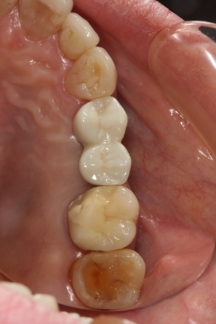

インプラントの埋入方向悪いため歯冠部の形態がおかしくインプラント周囲炎を起こしている

最終補綴物はインプラント補綴の経験豊富な技工士によって制作させていただきます。